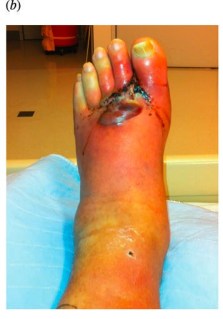

That said, medical practitioners are finding interesting, novel ways to use existing (and commonplace) technology. Millions of people across the globe use the iPhone (including myself). One article** I found on PubMed described how physicians used the iPhone 4 FaceTime software to videochat with each other and share images of a patient’s foot that had a limb-threatening infection, and needed emergency surgery. Here is a section of the article explaining what was done:

“A patient with a limb-threatening infection was taken on an urgent basis to the operating room. With no prior planning except for text messaging, the surgeon consulted with 2 surgical colleagues to discuss incision planning, requirements for resection, and subsequent surgical staging (Figs 2a–2d). The “FaceTime” application was managed by an operating room technician under the direction of the operating surgeon” (215).

And here are the images captured on the iPhone 4 (warning: these are a bit graphic).

If I had been that diabetic patient who needed emergency foot surgery, I would have been quite willing to have my surgeon consult with another surgeon via iPhone. If I were Deanna Ventura, didn’t drive, and lived too far to see the specialist I needed, I would be happy to see the physician over video conferencing. But if I could, I would still prefer to see a doctor in a face-to-face visit. That’s just me – I like the personal contact. There are times, though, when that’s just not possible. And that’s where telemedicine extends medicine’s reach.

**Armstrong, D.G., Giovinco, N., Mills, J.L., and Rogers, L.C. (2011). FaceTime for Physicians: Using Real Time Mobile Phone-Based Videoconferencing to Augment Diagnosis and Care in Telemedicine. Eplasty 11, e23-e23.